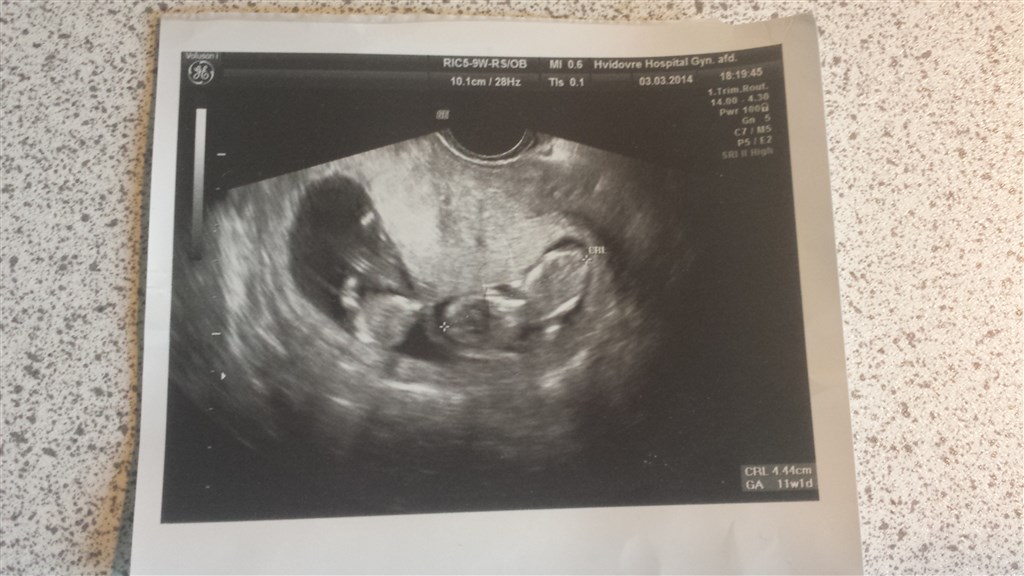

Det er vores scannings billed da jeg var 11+5 med tvillinger. Da vi fandt ud af det

Skal til NF imorgen 13+3 så er spændt på hvordan det ser ud.

Vedhæftede fotos (klik for at se i fuld størrelse)